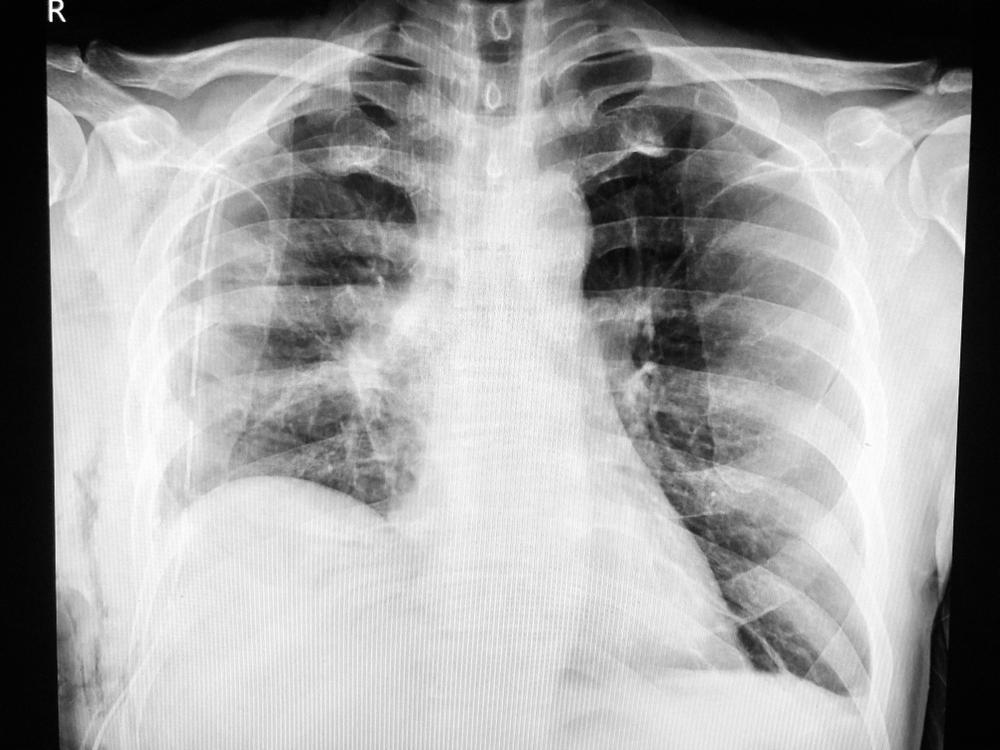

Trong ngày đặt ống dẫn lưu màng phổi, bác sĩ sẽ chỉ định chụp X quang phổi và giải thích cho bạn tại sao cần thực hiện thủ thuật này.

Cuối cùng, bác sĩ sẽ cho bạn chụp phim X-quang lại lần nữa để xem thử không khí và dịch đã được rút hết hay chưa.